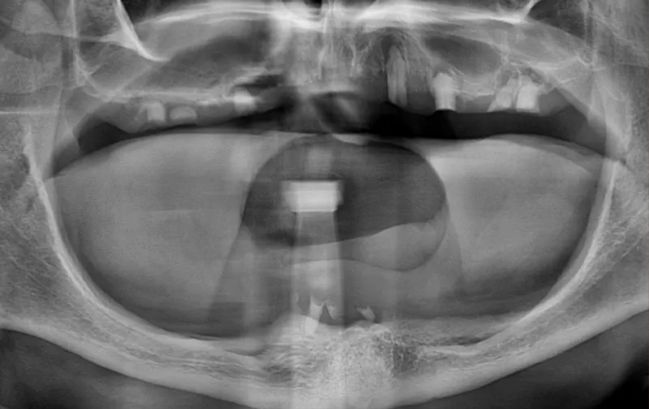

50대 남성, 원데이 앞니 임플란트